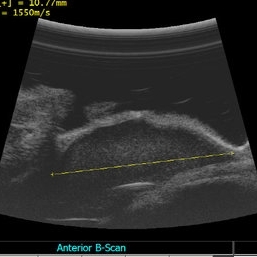

Ciliary mass ultrasound

Immersion ultrasound of mass shows cystic lesion 11mm in diameter

Condition/keywords: ciliary body mass, cystic lesion, immersion ultrasound